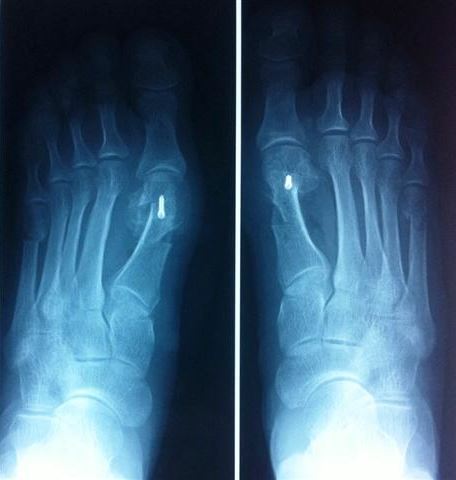

В нашей клинике применяется система малоинвазивных операций, разработанная одним из апологетов хирургии переднего отдела стопы – французским ортопедом L. Barouk. Операция заключается в многоплоскостных остеотомиях (пересечение кости) плюсневых костей с целью воссоздания поперечного свода стопы. Смещенные фрагменты плюсневых костей под рентген-контролем при помощи современного электронно-оптического преобразователя фиксируются специальными внутрикостно-устанавливаемыми мини-винтами, не требующими в дальнейшем их удаления.